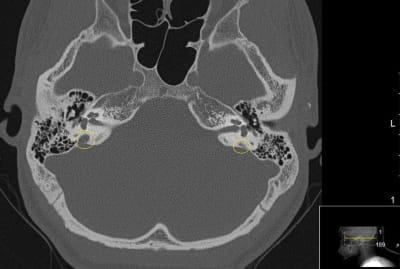

It’s a clinical conundrum: An enlarged vestibular aqueduct (EVA) is the most common inner ear malformation linked to sensorineural hearing loss in children. Yet pediatric otolaryngologists know relatively little about how and why EVA syndrome progresses to hearing loss – and which interventions might stop the process. Some patients develop profound hearing loss, while others do not – a difference seemingly unrelated to the size of the EVA.

The dearth of patient data may be a result, at least in part, of past limitations in imaging EVA. Until recently, Dr. Otteson says, imaging technology was inadequate to accurately characterize an EVA.

“Our data on EVA is only as good as the accuracy of our imaging,” he says. “Vestibular anatomy has a size on the order of millimeters. But advances in technology have allowed us to hone in on a clear characterization. The increasing resolution of CT scans in recent years has increased diagnosis and recognition of EVA syndrome.”